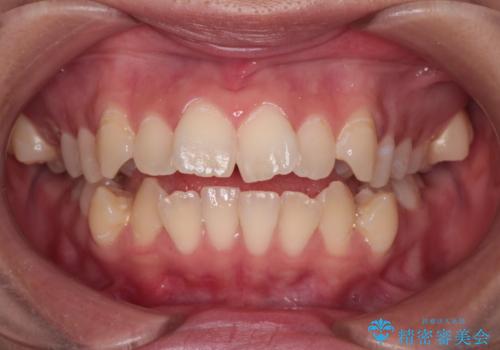

【インビザライン】シザーズバイト、抜歯矯正

- オープンバイトを主訴に来院された患者様です。

抜歯を行うことで、インビザラインを用いて前歯を下げることができ、同時にオープンバイトを改善することができました。

今回はインビザラインのみで治療を終了することができました。